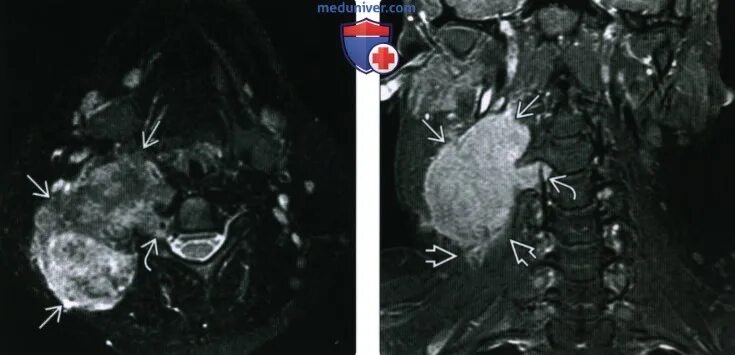

Мрт симптомы